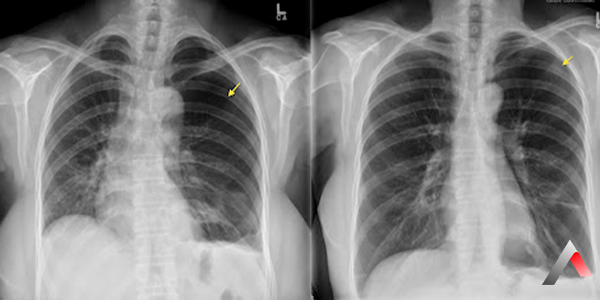

Pnömotoraks Tanısı

Pnömotoraks tanısı koymak için doktorunuz aşağıdaki testleri isteyebilir:

• Fizik Muayene: Göğsünüzü dinleyerek ve genel sağlık durumunuzu değerlendirmek için fizik muayene yapacaktır.

• Göğüs Röntgen: Akciğerlerinizin görüntüsünü elde etmek ve pnömotoraksı doğrulamak için göğüs röntgeni isteyebilir.

• Bilgisayarlı Tomografi (BT): Akciğerlerinizin daha detaylı görüntüsünü elde etmek ve pnömotoraksın boyutunu ve yerini belirlemek için BT isteyebilir.